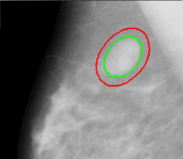

Figure 9: Localization of micro-calcifications in mammogram images taken from [33]. Left column shows initialization with elliptical templates, and right column shows the converged contours. Figures are cropped to show the region of interest.

We next conducted an experiment on a mammogram taken from the mini-MIAS database [33], which contains some benignant and malignant tumor images. The images (filename: mdb028) containing lumps as shown in Figure 9, were specifically classified in the database as circular in shape with a certain center and radius. We employed the elliptical shape template to localize the mass and measured the resulting dimensions of the fit. For the top row, the converged ellipse fit was found to have a semi-major and semi-minor axes of 58 and 56 pixels, respectively. The radius of the approximate circumscribing circle was given in the database as 56 pixels. The center of converged contour matches the one given in the database. For the bottom row, semi-major and semi-minor axes are 64 and 42 pixels, whereas the true radius is 68. The center of the converged snake differs by 4 pixels in both horizontal and vertical directions from that given in the database.